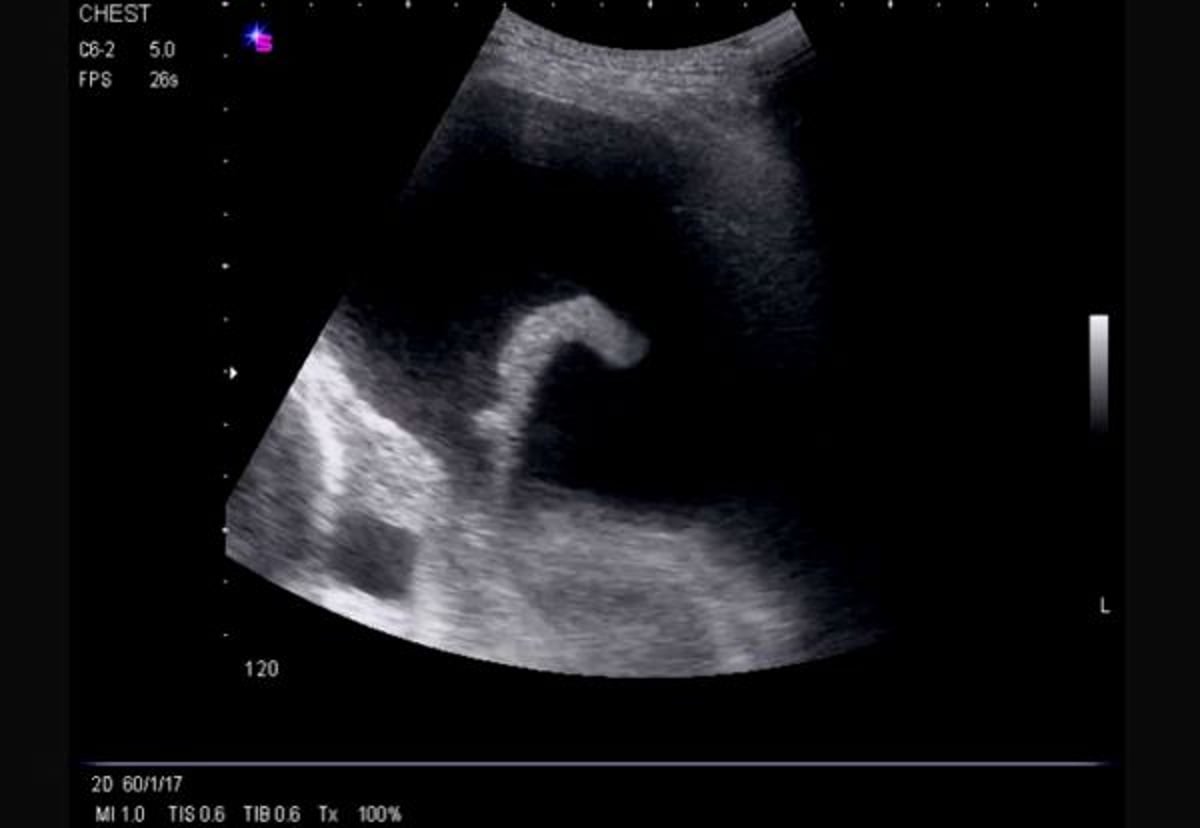

Ultrassom torácico lateral (esquerda)

Essa ultrassonografia mostra um derrame de fluxo livre e extenso do lado esquerdo, causando atelectasia compressiva do lobo inferior esquerdo e revelando o ventrículo esquerdo.

Imagem cedida por cortesia de Najib M. Rahman, BMBCh MA (oxon) DPhil.